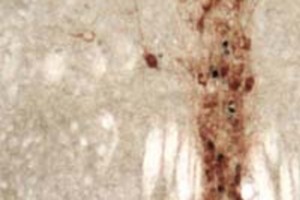

Come mosta l’immagine concessa da Christopher Lowry nella pubblicazione su Discovery Magazine, nella sezione del cervello al microscopio, le macchie blu rappresentato il rilascio della serotonina, attivata dal microbo del suolo.